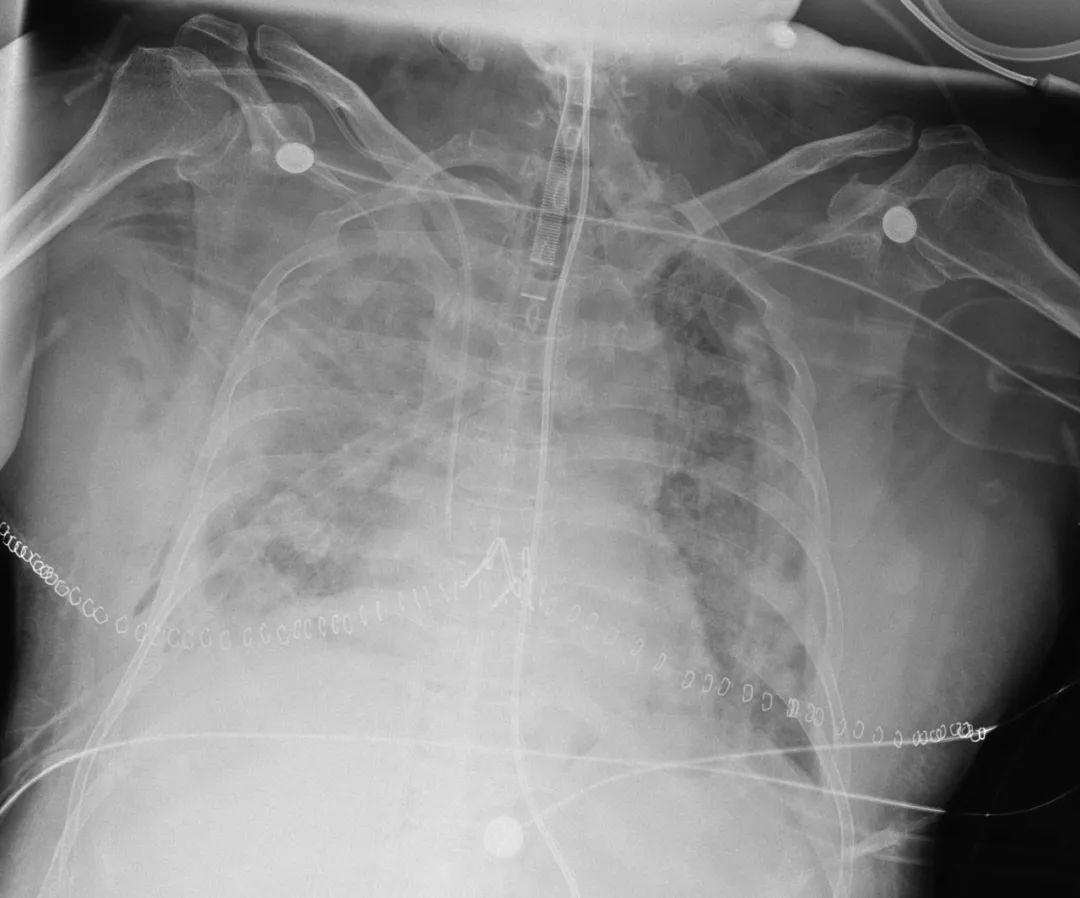

▼女病患術前肺部嚴重受損,X光呈現一片白。(圖/翻攝自澎湃新聞)

負責操刀的著名肺移植專家、浙江大學醫學院附屬第一醫院肺移植科主任韓威力表示,當時打開患者胸腔後,看到肺部受損的狀況,當場大吃一驚,「病人整個肺是紫色的,還硬邦邦,萎縮得只有正常肺的一半大,還有大量黏液。」他指出,平時只要花半個小時就能切下一側的肺,這次足足花了一個半小時,「患者體型比較豐腴,胸腔空間變小,肺窩在裡面,又有下垂,同時,患者的心臟又有擴大,嚴重影響視野。」

▼醫師打開女患者胸腔後,驚呼「整個肺是紫色的且硬邦邦,萎縮得只有正常肺的一半大。」(圖/翻攝自澎湃新聞)